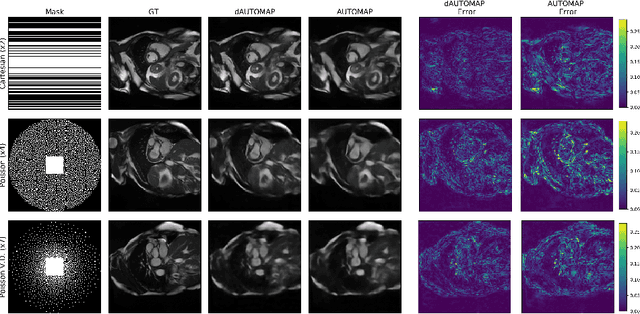

Abstract:AUTOMAP is a promising generalized reconstruction approach, however, it is not scalable and hence the practicality is limited. We present dAUTOMAP, a novel way for decomposing the domain transformation of AUTOMAP, making the model scale linearly. We show dAUTOMAP outperforms AUTOMAP with significantly fewer parameters.